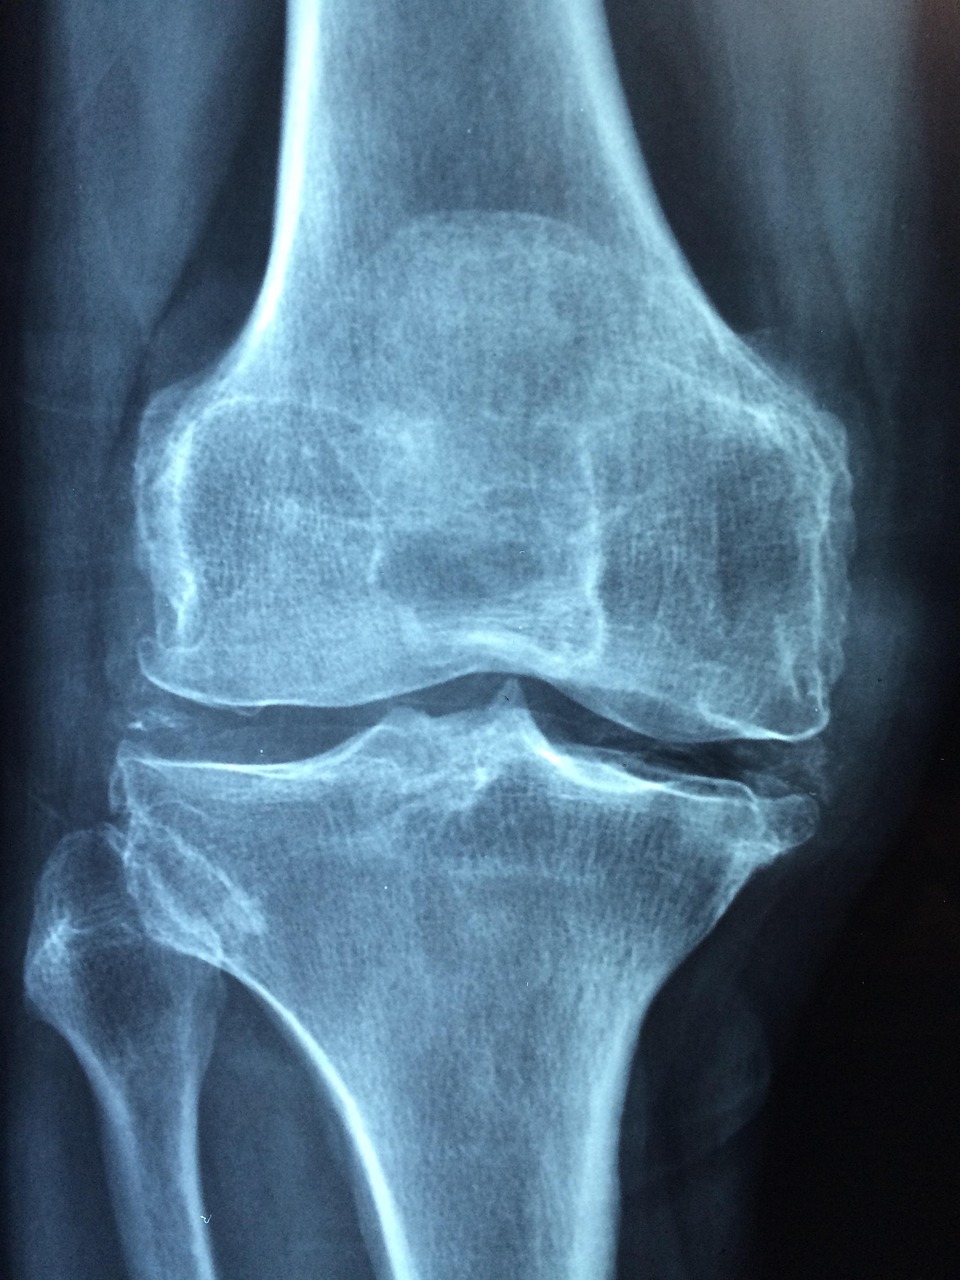

오금은 무릎 뒤쪽의 근육과 힘줄, 신경, 혈관이 모여 있는 중요한 부위로, 무릎을 굽히고 체중을 지탱하며 하체의 균형을 유지하는 데 핵심적인 역할을 합니다. 이 부위가 약해지면 무릎에 부담이 집중되어 통증이나 퇴행성 관절염이 생기기 쉬우며, 특히 중장년층은 활동량이 줄면서 오금 근육이 더 빨리 약화되는 악순환을 겪습니다. 또한 오금에는 주요 신경과 혈관이 지나가므로, 이곳이 경직되면 저림, 감각 이상 등의 증상이 발생할 수 있습니다. 등산이나 스쿼트처럼 무릎을 반복적으로 쓰는 활동에서는 오금에 가해지는 부하가 크기 때문에 꾸준한 스트레칭과 근력 운동이 필수적입니다. 오금은 평소에는 잘 느끼지 못하지만, 증상이 나타난 후에야 그 중요성을 깨닫게 되는 경우가 많습니다. 결국 오금이 튼튼해야 무릎이 튼튼하고, 무릎이 튼튼해야 자유롭게 걸을 수 있기 때문에, 오금 근육을 지금부터라도 관리하는 것이 건강한 노후를 위한 시작이라 할 수 있습니다.

오금이 약해지면 무릎 통증이나 불편함이 점점 잦아지며, 일상생활에 큰 영향을 줄 수 있습니다. 오금은 무릎 뒤쪽에 위치한 근육과 힘줄, 신경, 혈관이 밀집된 부위로, 무릎을 굽히고 펴는 움직임뿐만 아니라 체중을 지탱하고 하체 균형을 유지하는 데도 중요한 역할을 합니다. 이 부위의 근력이 약해지면 평지를 걷는 것조차 무릎이 불안정하게 느껴지거나, 계단을 오르내릴 때 찌릿한 통증이 발생하기 쉽습니다. 또한 장시간 앉아 있다가 일어날 때 무릎이 굳거나 관절이 잘 펴지지 않는 느낌도 생길 수 있습니다. 오금의 약화는 무릎 연골에 부담을 주어 퇴행성 관절염을 유발할 수 있으며, 특히 중장년층 이상에서는 활동량이 줄면서 하체 근육 전반이 약해지고 낙상의 위험도 높아질 수 있습니다. 오금에는 주요 신경과 혈관이 지나가기 때문에 이 부위가 약해지면 저림, 감각 저하 등의 신경 증상도 나타날 수 있습니다. 많은 분들이 오금의 중요성을 인식하지 못한 채 단순한 무릎 통증으로 넘기지만, 오금을 강화하는 스트레칭과 근력 운동만으로도 이러한 불편을 예방하고 줄일 수 있습니다. 지금부터라도 오금 근육을 꾸준히 관리하신다면 건강한 보행과 활동적인 삶을 지키실 수 있습니다.